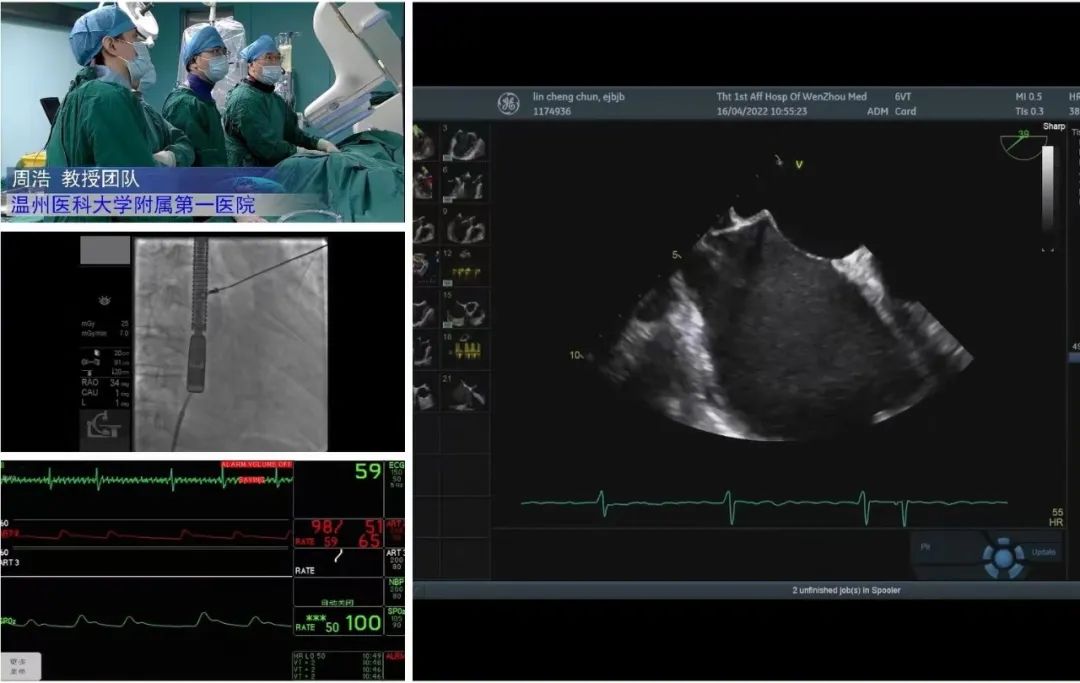

患者全身麻醉后,建立右侧股静脉入路,在经食道超声指导下精准穿刺房间隔。

将可操控导引导管和瓣膜夹输送系统送入左心房

调整二尖瓣夹,使其定位于反流6-12点钟方位